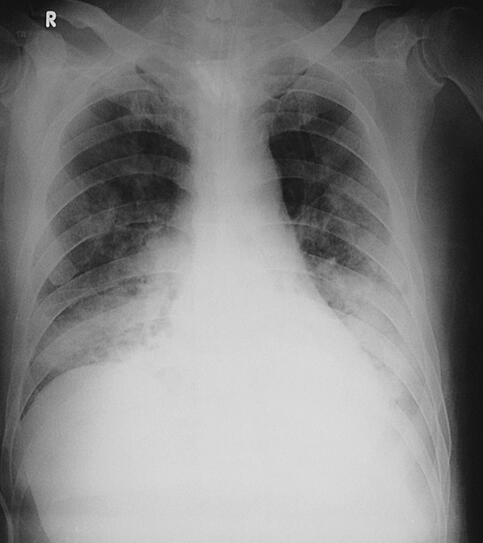

诊治经过:患者入笔者科室后一般情况较差,血压测不出,氧饱和度84%,予以羟乙基淀粉扩容,多巴胺、去甲肾上腺素微泵维持血压,碳酸氢钠纠正酸中毒。立即予以气管插管,呼吸机辅助通气。完善相关检查:CT(图1)结果:①头颅CT平扫未见明显异常;②双下肺肺不张;③双侧胸腔积液;④肝右叶钙化灶。血常规(2月7日):WBC 20.9×109/L,N 94%。心脏彩超(2月8日):左心室舒张末内径61mm,射血分数38%。胸片(图2~图4)诊断:①双侧肺炎;②颈椎术后。先后给予头孢曲松钠和左氧氟沙星、美罗培南和替考拉宁抗感染。因痰培养鲍曼不动杆菌(2月10日),对头孢哌酮-舒巴坦钠敏感,余均耐药,故停用美罗培南,改用头孢哌酮-舒巴坦钠。多次血培养结果提示白念珠菌(2月6日、2月7日、2月9日、2月10日),对氟康唑和伊曲康唑均敏感,因为患者肌酐高,肾功能异常,故给予米卡芬净和氟康唑抗真菌治疗。患者血糖高,2月6日末梢血血糖33.1mmol/L,给予胰岛素强化治疗,但是血糖控制不佳,一直在11mmol/L以上。同时给予化痰、抗炎、保肝、营养神经、调节机体免疫、加强营养、维持内环境稳定、对症支持等治疗。

图4 2月13日胸片

治疗和转归:患者病情曾一度好转,2月10日停用血管活性药物后血压维持在130/80mmHg左右,血常规白细胞计数和中性粒细胞较前明显下降。但患者多次血培养结果提示白念珠菌,痰培养鲍曼不动杆菌,抗真菌和抗感染效果不佳,逐渐出现了多脏器功能衰竭(循环、肺、肾、血液系统)。大剂量血管活性药(多巴胺和去甲肾上腺素)维持下,心率、血压进行性下降,呼吸机吸氧浓度100%,但氧饱和度也只有60%~70%,于2月15日自动出院。